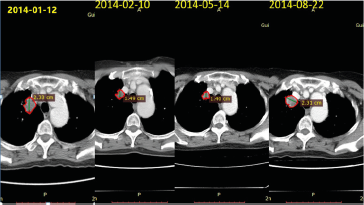

#Individualizedtreatment for a Patient with Advanced#NSCLC by Shaozhong He in#BJSTR https://biomedres.us/fulltexts/BJSTR.MS.ID.003264.php … Follow on blogger : https://biomedres01.blogspot.com Like our pins on :: https://pinterest.com/biomedres/ pic.twitter.com/UPHmYiYo4s